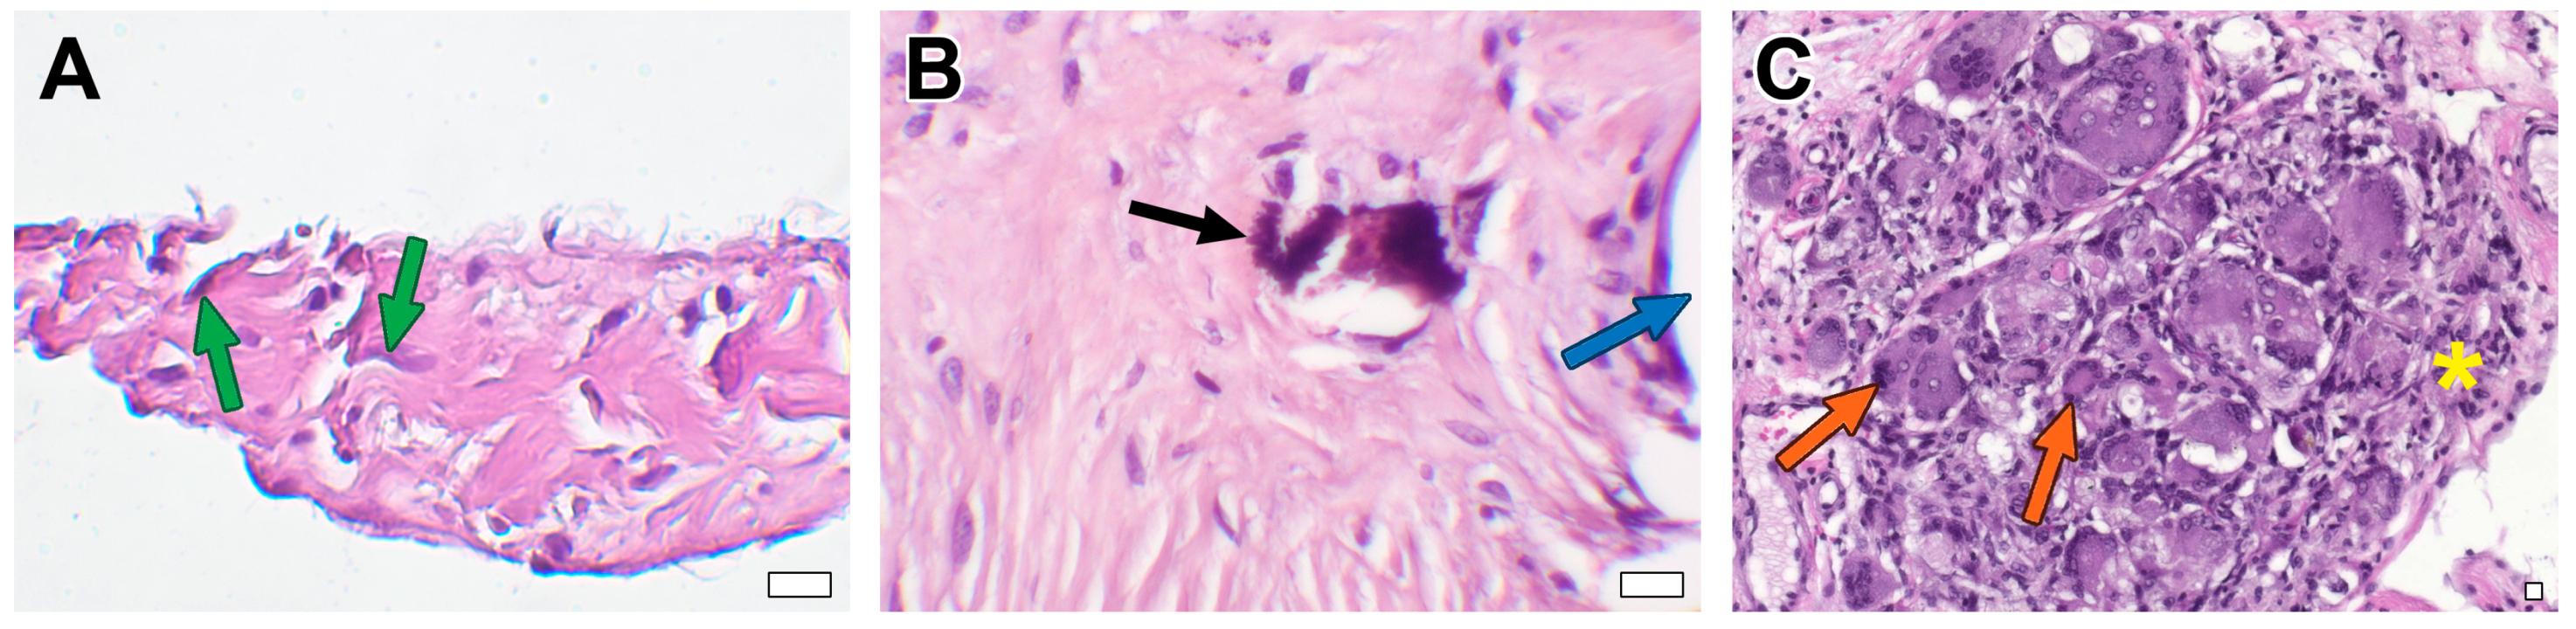

3.2. Microscopic Examination